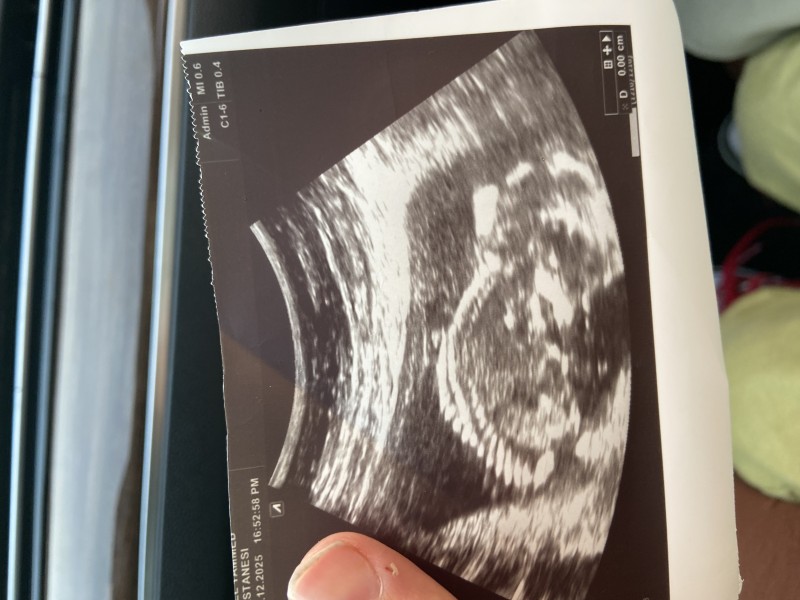

Kızlar ben 12+5 günlükken cinsiyet için doktora gittiğimde doktor bebeğinbacak arasını tamamen boş görmüştü iki haftaya belli olur demişti ben de iki haftaya yakın bir sürede tekrar doktora gittiğimde bana pipisini gördüğünü söyledi sonra pipi değil kordon olabilir bu dedi kontrol olarak geçti haftaya gel dedi bugün de gittim o kadar umursamaz o kadar çok rahattı ki hatta ultrasona bakmayacaktı bile ilaç yazıp gönderecekti ben dedim hocam cinsiyete bakar mısınız diye baktı bacak arasına baktı yani hiç değişmemiş dedi  tekrar kordon olabilir bu gene dedi niye merak ediyorsunuz dedi kız olabilir erkek olabilir niye peşine düşüyorsun dedi doğduktan sonra zaten görürsün dedi aşırı derecede moralim bozuldu aşırı derecede üzüldüm hani sanki cinsiyeti biliyormuş gibi biliyor da bana söylemiyormuş gibi muamele etti atıyorum kız dedi ne yapacaksın dedi erkek olsa ne yapacaksın dedi ben de dedim ki ne hocam bana ultrason görüntüsünü net bir şekilde verin bana verdiği ultrason görüntüsüne bakın ve hiçbir şekilde ölçümleri sisteme girmedi ölçümleri de ultrason üzerine yazmadı oğlum da aynı haftada daha erken haftaydı hatta bana %100 erkek demişti bunda hani içimden kız geliyor benim ailem çok namazlı abdestli özellikle babam maneviyatı çok yüksek hani benim inancım var ve ben bunu söyledim hocam dedim çok fazla rüya görüyorlar çok fazla kız hissediyorlar bana diyor ki sen geç geçiyor o işleri o işler boş işler hani çok çok ters cevaplar verdi benim çok moralim bozuldu başına böyle bir olay gelen var mı sizce cinsiyet nedir ultrason görüntü

Öyle yapıcam canım yeni açılan bir hastane vardı oraya gidicem cihazları yenidir belki daha net belli olur ama 14. Haftada net olması gerekiyor değil mi ben oğlumda daha erken öğrenmiştim bu haftada pipi kordonla nasıl karışılır anlamadım

Canım 3 hafta önce gittiğimde 12 haftalıktı üç haftadır pipi diyo sonra kordon da olabilir diyo şunan 14 haftalığım

Canım erkek gibi ya benim oğlumun da böyle pipisi vardı anlaşılıyor du tıpkı seninkisi gibi ama yinede bilemiyorum bence erkek tahmini

Hayırlısı canım inşallah merakla bekliyorum bende bir önceki hafta attığımda herkes kız demişti ama ben hiç bişey anlamadım bebeği bile göremedim ultrasonda